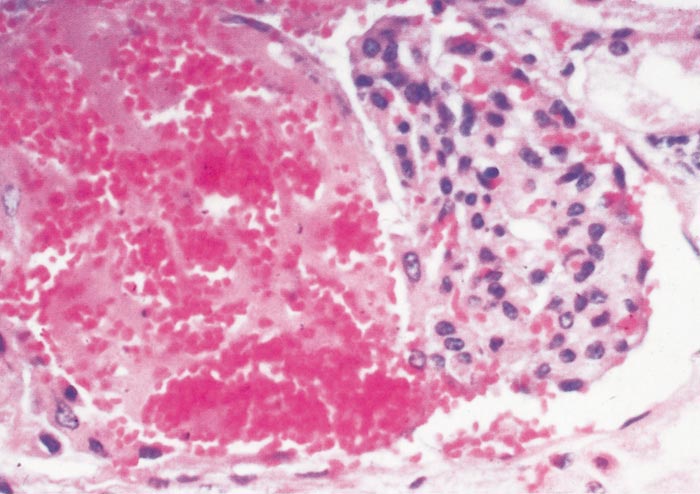

Lesions in target organs such as the liver in the acute disease are produced by the direct lytic effect of the virus on infected cells. In the liver of new-born lambs, for instance, there is initial cloudy swelling and hydropic degeneration of randomly scattered hepatocytes, which soon become necrotic as manifested by acidophilic cytoplasm and pyknotic nuclei. The lesions rapidly progress to form scattered primary necrotic foci of five to eight affected hepatocytes, with the presence of acidophilic cytoplasmic or apoptotic bodies resulting from cytolysis, and infiltration of neutrophils. As the primary lesions enlarge, numerous degenerated and necrotic hepatocytes and acidophilic bodies appear throughout the parenchyma. Ultimately there is massive necrotic hepatitis in which the residual primary foci can still be recognized as dense aggregates of cellular debris infiltrated by leukocytes.117, 168

The haemostatic derangement that occurs in RVF has been investigated in detail only in rhesus monkeys, and the mechanisms involved remain speculative.125, 497 Impairment of coagulation occurs even in benign infection in monkeys,125, 497 and it is notable that moderate thrombocytopenia has been observed in benign infection in sheep.595 However, haemostatic derangement is most severe in the fatal hepatic syndrome, which manifests as a viral haemorrhagic fever with bleeding tendency and evidence of disseminated intravascular coagulopathy.125 Viraemia is intense and prolonged in individuals that develop the haemorrhagic syndrome, indicating that there is impaired clearance of viraemia and extensive dissemination of virus with attendant widespread tissue damage, and it is postulated that the critical lesions in the development of the haemorrhagic state are vasculitis and hepatic necrosis.125, 497, 498 Destruction of the antithrombotic properties of endothelial cells is thought to trigger intravascular coagulation, and the widespread necrosis of hepatocytes and other affected cells to result in the release of procoagulants into the circulation. Severe liver damage presumably limits or abolishes production of coagulation proteins and reduces clearance of activated coagulation factors, thereby further promoting the occurrence of disseminated intravascular coagulopathy, which in turn augments tissue injury by impairing blood flow. Vasculitis and haemostatic failure result in purpura and widespread haemorrhages.